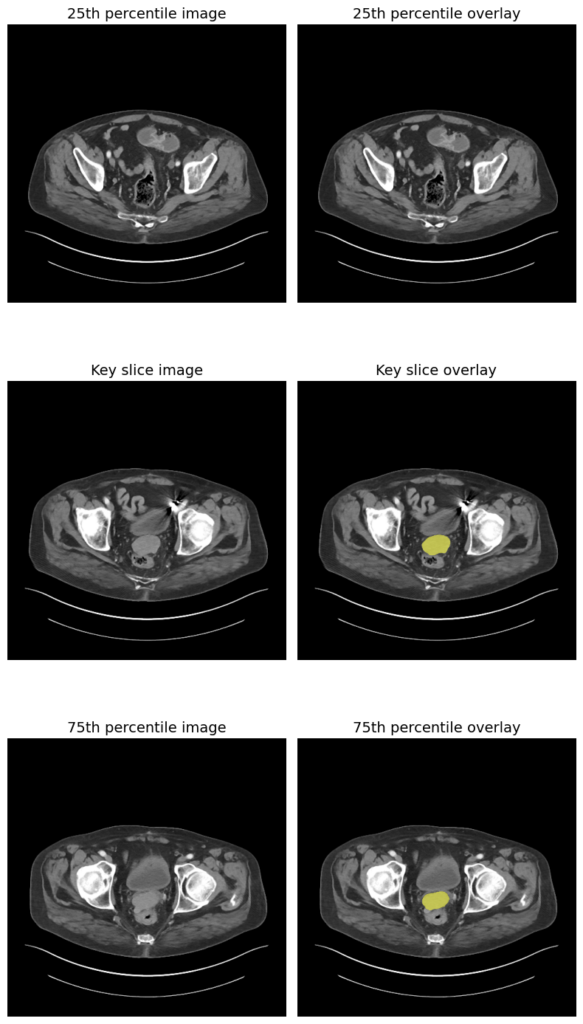

在这里,我们将对 骨盆 的 3D CT 扫描图像 进行处理,查看 轴向切片(水平横截面),并尝试使用 MedSAM2 分割病变(可能是前列腺肿瘤)。

以下是结果:

骨盆病变的 3D CT 分割

可以看到模型在骨盆中分割了一个小结构,很可能是 膀胱 或者可能是 前列腺肿瘤 或 盆腔肿块,具体取决于临床任务。这不是很酷吗!这可以为医生和外科医生节省大量时间,帮助他们快速做出决策,从而拯救数百万生命,使我们的医疗系统更加智能和高效。